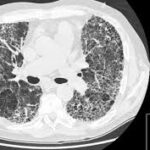

The HRCT lungs scan is an advanced test that provides clear and detailed pictures of the lungs, helping doctors understand how healthy the lungs are. It helps find different lung problems like pneumonia, scarring, lung damage, chronic breathing problems (COPD), and even lung cancer. This non-invasive HRCT chest scan is important for finding lung problems that may not show up in regular X-rays. By using a high-quality CT scan for lungs, doctors can look at the lung structures closely, allowing for accurate diagnoses and prompt treatment.

An HRCT lung scan is a detailed test that takes clear images of the lungs using modern CT scan equipment. It is mainly used to identify lung diseases, find lung issues, and assess the level of conditions like lung scarring, lung damage, long-term lung disease, and cancer in the lungs. This scan provides a better view in comparison to a standard chest X-ray. It helps find problems with the lungs, such as swelling, infections, and changes in the lung structure. The test might use a dye to make the images clearer, helping doctors identify lung problems more easily.